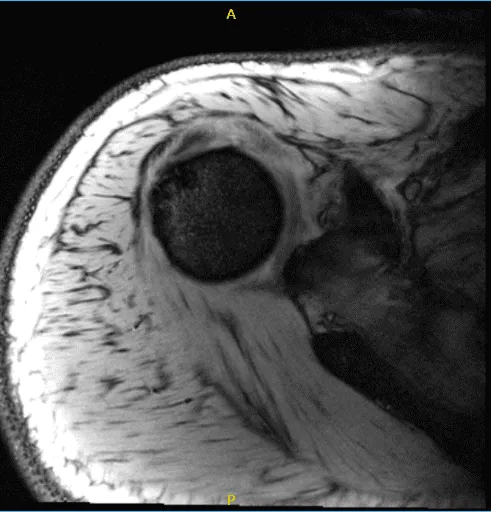

His MRI showed an impression as follows: Focal grade 1 partial-thickness tear of the infraspinatus tendon at the footprint with adjacent small traction cysts. Intact labrum and biceps tendon. Widening of the AC joint suggestive of chronic AC joint separation versus a previous. Mumford procedure. Correlate with surgical history.

MRI of the right shoulder